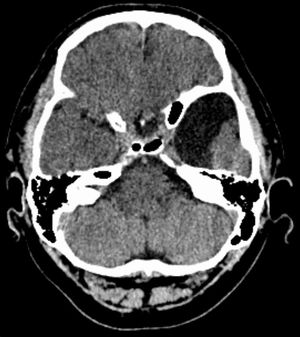

진단은 주로 MRI로 이루어진다. 지주막낭종은 다른 임상적 이유로 MRI를 촬영하는 과정에서 우연히 발견되는 경우가 많다.[9] 실제적으로 증상이 있는 지주막낭종을 진단하려면 증상이 나타나야 하며, 이 질환을 가진 많은 환자는 평생 증상이 나타나지 않는다.

지주막낭종 진단은 주로 MRI로 이루어진다.[9] 지주막낭종은 다른 임상적 이유로 MRI를 촬영하는 과정에서 우연히 발견되는 경우가 많다.[9] 실제적으로 증상이 있는 지주막낭종을 진단하려면 증상이 나타나야 하며, 이 질환을 가진 많은 환자는 평생 증상이 나타나지 않는다.

지주막낭종은 뇌 또는 척추에서 발견될 수 있다. 두개내 지주막낭종은 대개 지주막하 낭포에 인접하여 발생한다.[23] 척추 지주막낭종은 경막외, 경막내 또는 신경주위에 위치할 수 있으며, 신경근병증을 시사하는 징후와 증상을 나타내는 경향이 있다.[23]